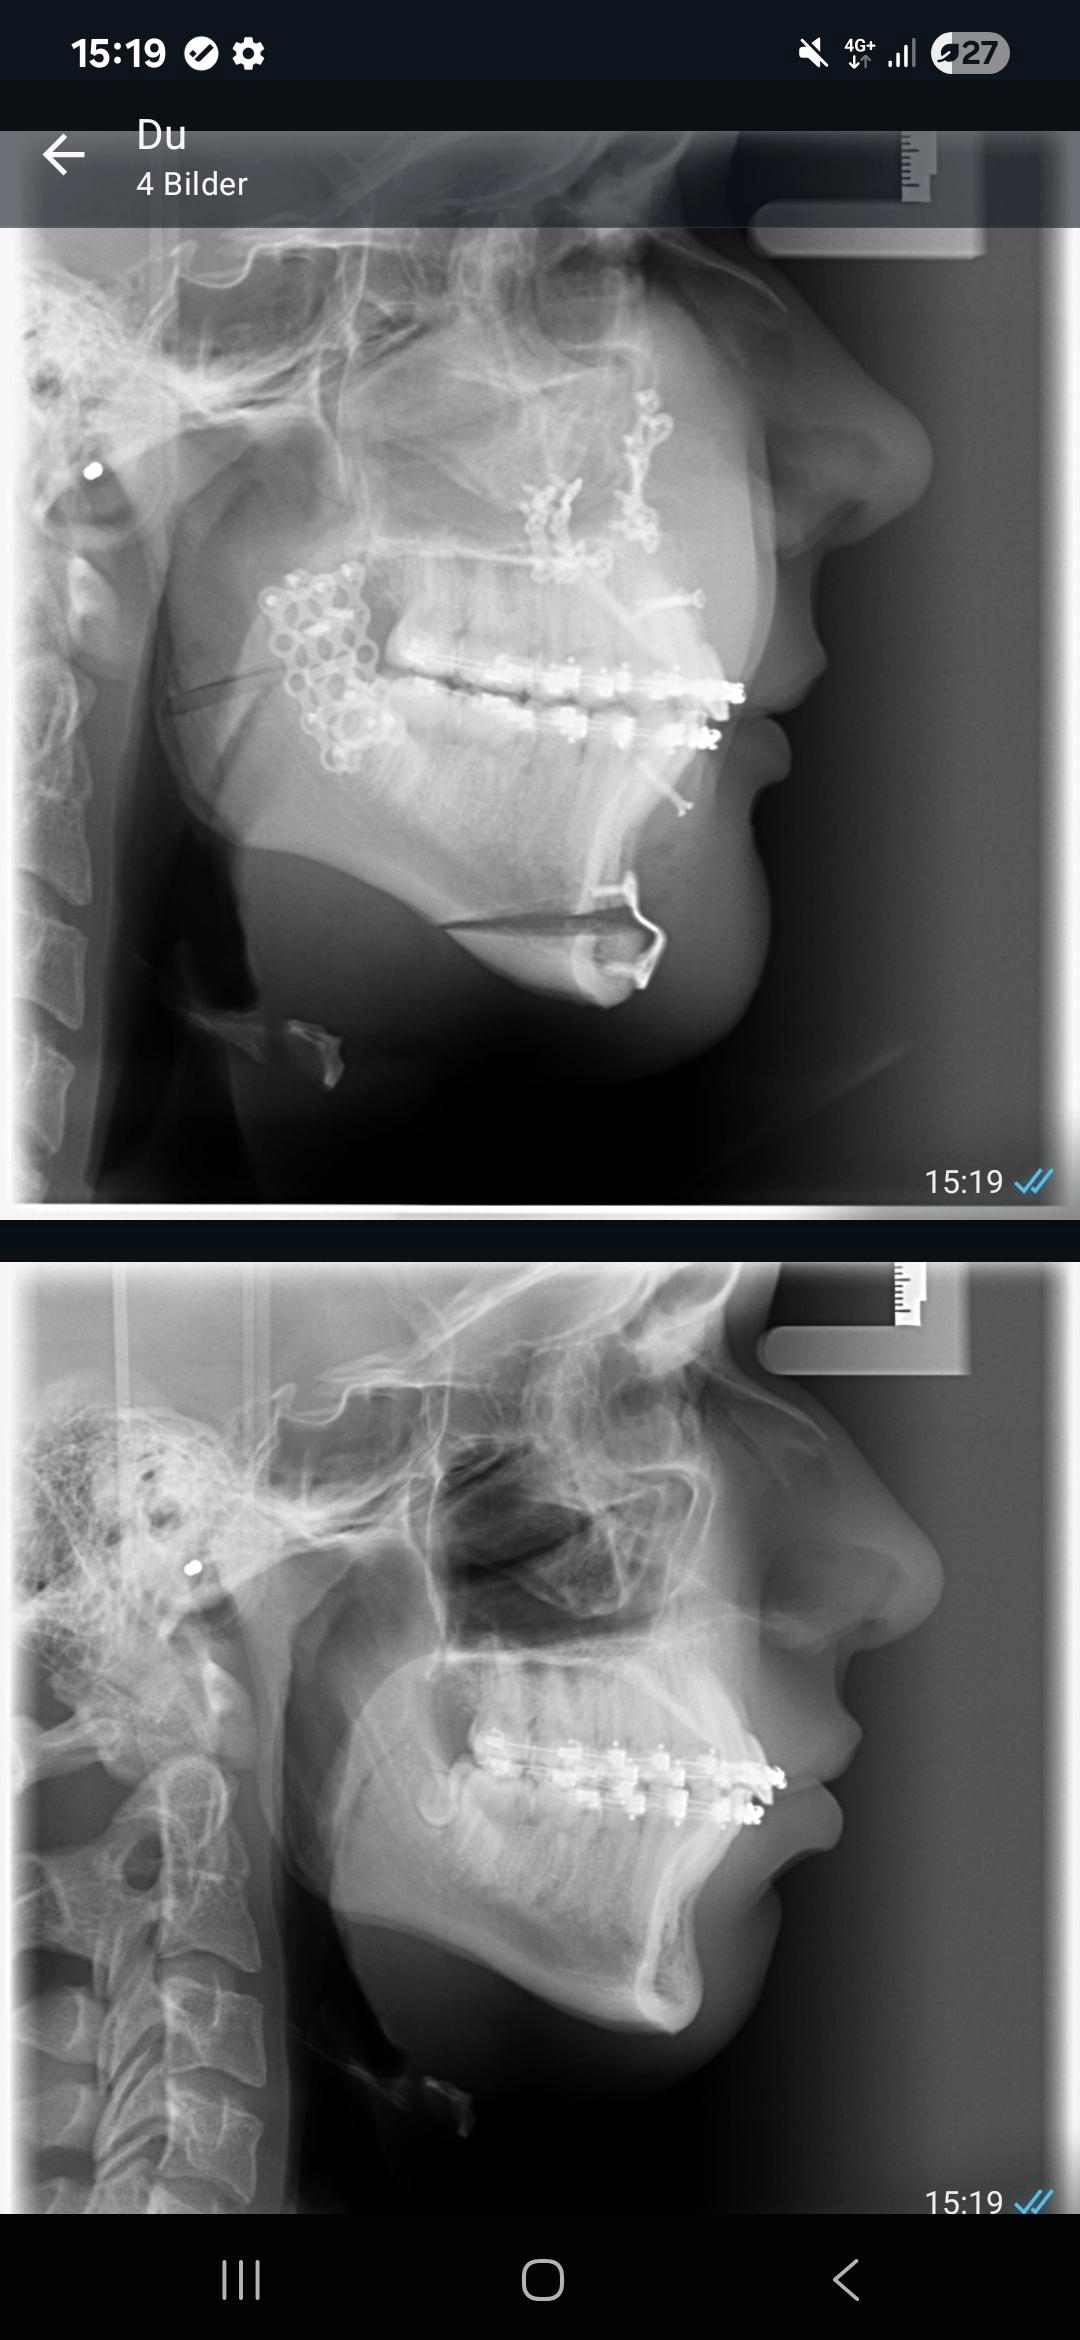

Some before and after pics, what do yall think? (still very bloated), it was 5 days ago and i'm 17

Before:

After:

look at the x ray faggot, nothing fucking changed, nigga got a botched genioplasty im fucking dead

the genioplasty had to be moved 3mm downwards because i had short face syndrome

how good/bad do you think my bimax went?

1770627749810

Bro you gotta be fucking kidding me @sayonara @Gargantuan nigga better sue his surgeon atp

You ascended judging from your X-rays. You just need to wait until your swelling fully goes away.